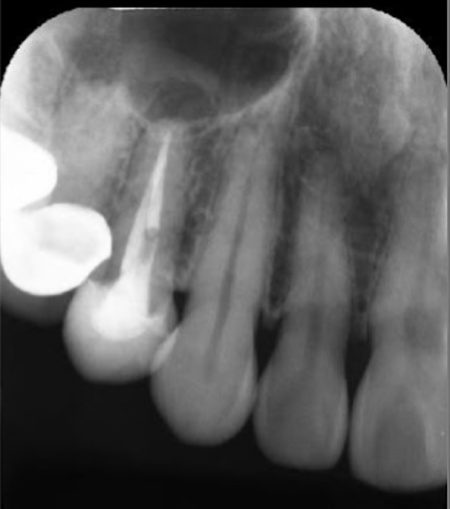

40代女性 炎症を起こした右上奥歯にマイクロスコープを用いた精密根管治療を行った症例

拝見したところ、右上奥歯(第2小臼歯)には保険診療の白い被せ物であるCADCAMが装着されていました。

レントゲン撮影をして検査すると、その手前の右上奥歯(第1小臼歯)には神経や血管が通る根管に清掃と消毒を行う根管治療が施されていました。しかし、歯の内部に細菌が侵入して炎症を起こし、歯根の先に膿が溜まる根尖病巣(こんせんびょうそう)を発症している状態です。

以上のことから、右上奥歯(第1小臼歯)を早急に治療する必要があると診断しました。

まず、唾液に含まれる細菌や血が根管内に入るのを防ぐため、ラバーダム(ゴム製のシート)で患部周辺を覆って治療部位だけを露出させ、マイクロスコープで確認しながら感染部位を丁寧に除去します。

根管内が清潔になったことを確認したら、再び細菌が入り込まないようしっかりと薬を詰めました。

レントゲン撮影で根尖病巣の治癒を確認後、最終的な被せ物を作製するため、歯の形を整えてから型取りを行います。